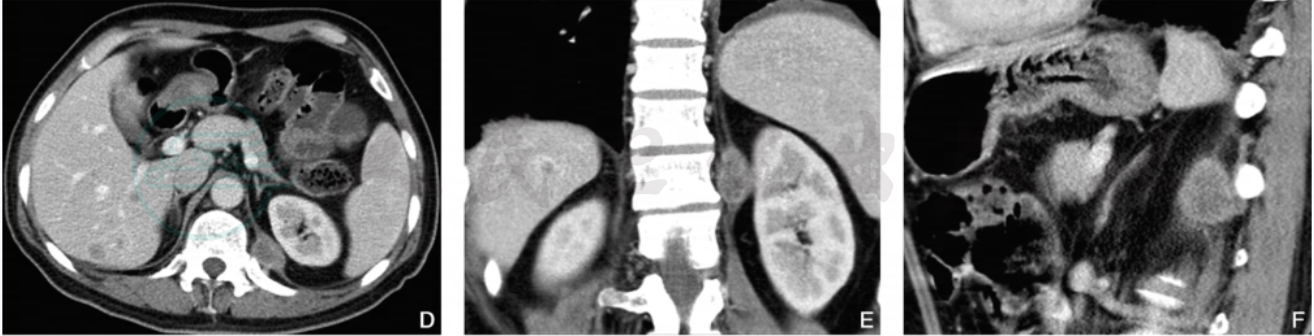

图3 膈肌转移瘤、肝脏转移瘤(肺癌)

注:男性,56岁,CT增强横断面动脉期(A)及静脉期(D)示左侧膈肌脚有一类椭圆形结节影,密度不均,冠状位重建动脉期(B)、静脉期(E)及矢状位重建(C)、静脉期(F)显示结节与膈肌脚关系;此外,肝右叶下段可见一小转移瘤结节。